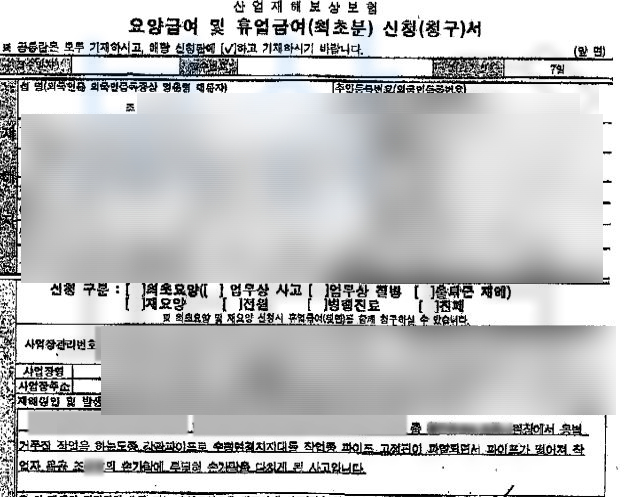

먼저 산재 신청을 하시게 되면 주치의의 치료 계획에 따라 산재 요양 기간이 결정되게 됩니다. 그 기간 동안의 치료비나 입원비 보상이 요양급여 입원, 통원 모두 포함한 기간의 급여 보상이 **휴업급여 ** 향후 신체에 잔존하게 된 손실에 대한 보상이 **장해급여 **

(요양기간동안 일을 하시게 되면 보수받은 부분은 제외하고 휴업급여 지급이 됩니다.) 조@@님은 처음 겪는 사고이고 향후 자신의 장해에 대한 올바른 보상을 위해 보상파트너에 연락주셨고 저희는 상주하는 노무직원을 통해 산재 장해급여 청구를 위임받아 요양기간동안의 관리와